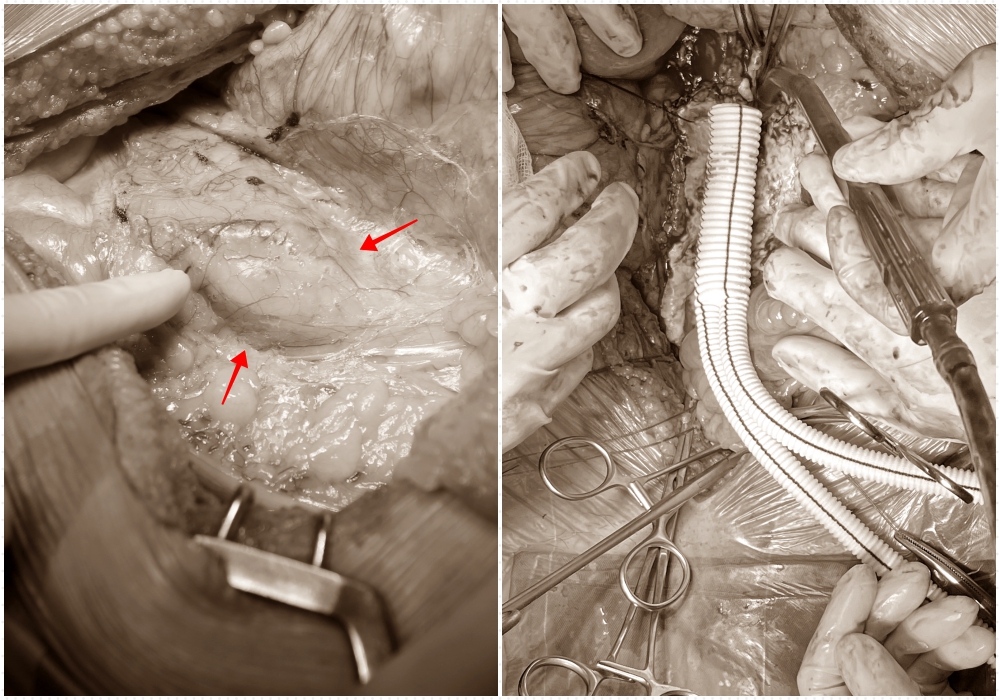

Khối phình động mạch chủ bụng được loại bỏ và thay bằng đoạn mạch nhân tạo

Kíp phẫu thuật mạch máu tiến hành mở bụng, phẫu tích bộc lộ động mạch chủ bụng thấy khối phình hình thoi đường kính khoảng 5,5 cm thành mỏng, các mảng xơ vữa lan xuống động mạch chậu gốc hai bên. Kíp mổ kẹp tạm động mạch chủ bụng, mở dọc khối phình lấy các tổ chức huyết khối, tiến hành cắt bỏ đoạn mạch tổn thương rồi dùng đoạn mạch nhân tạo hình chữ Y để nối động mạch chủ với hai động mạch chậu, cắm lại các mạch phụ. Sau khi kiểm tra miệng nối thông tốt không thấy thiếu máu ruột, kíp mổ tiếp tục mở bể thận trái lấy sỏi. Cuộc mổ diễn ra thành công thuận lợi sau 3 giờ phẫu thuật. Sau mổ, sức khỏe bệnh nhân tiến triển tích cực, tỉnh táo, phục hồi nhanh, các chỉ số ổn định.